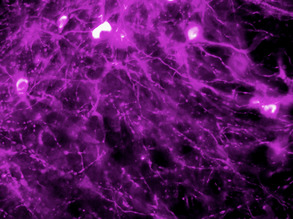

Mending Myelin